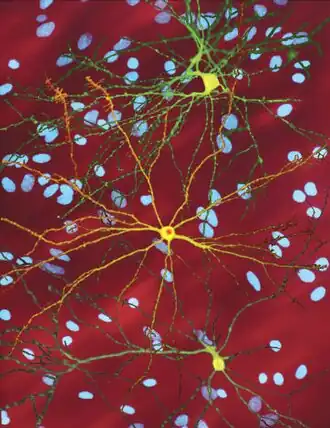

The toxic action of mHtt may manifest and produce the HD pathology through multiple cellular changes.[52][53] In its mutant (polyglutamine expanded) form, the protein is more prone to cleavage that creates shorter fragments containing the polyglutamine expansion.[52] These protein fragments have a propensity to undergo misfolding and aggregation, yielding fibrillar aggregates in which non-native polyglutamine β-strands from multiple proteins are bonded together by hydrogen bonds.[15] These aggregates share the same fundamental cross-beta amyloid architecture seen in other protein deposition diseases.[54] Over time, the aggregates accumulate to form inclusion bodies within cells, ultimately interfering with neuronal function.[15][52] Inclusion bodies have been found in both the cell nucleus and cytoplasm.[52] Inclusion bodies in cells of the brain are one of the earliest pathological changes, and some experiments have found that they can be toxic for the cell, but other experiments have shown that they may form as part of the body's defense mechanism and help protect cells.[52]

A somatic expansion of CAG repeats is involved in the progression of the disease. Over decades, the HTT gene first sees its CAG repeats expand to about 80 copies: the 35+ CAG locus causes additional slippage errors that expand the repeat. Then the process accelerates, reaching 150 copies within years. There is no significant toxic effect on the cell until 150 copies, at which point a large number of genes become progressively dysregulated. Over months, the medium spiny neuron slowly loses its cell identity until cell death pathways are activated.[57]

Initially, damage to the brain is regionally specific with the dorsal striatum in the subcortical basal ganglia being primarily affected, followed later by cortical involvement in all areas.[58][59] Other areas of the basal ganglia affected include the substantia nigra; cortical involvement includes cortical layers 3, 5, and 6; also evident is involvement of the hippocampus, Purkinje cells in the cerebellum, lateral tuberal nuclei of the hypothalamus and parts of the thalamus.[29] These areas are affected according to their structure and the types of neurons they contain, reducing in size as they lose cells.[29] Striatal medium spiny neurons are the most vulnerable, particularly ones with projections towards the external globus pallidus, with interneurons and spiny cells projecting to the internal globus pallidus being less affected.[29][60] HD also causes an abnormal increase in astrocytes and activation of the brain's immune cells, microglia.[61]